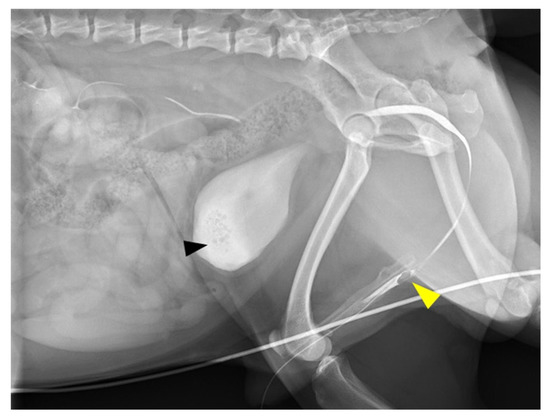

Dysuria was the only complaint at initial consultation. No abnormality was detected on physical examination. Complete blood count (CBC) revealed slight leukocytosis (204 × 102/μL; reference range, 60–170 × 102/μL), and biochemical analysis showed postprandial mild hyperammonemia (fasting: 33.8 mg/dL, postprandial: 84.0 mg/dL; reference range, 16.0–75.0 mg/dL) and high total bile acid concentration (fasting: 19.3 mg/dL, postprandial: 90.3 mg/dL; reference range, 0–5.0 mg/dL). On survey radiography, many small calculi were seen in the urinary bladder. No calculi were seen in the urethra. Radiography and ultrasonography revealed microhepatia and hypoplasia of the hepatic portal vein. The insertion of the urethral catheter was relatively difficult, but a 4-Fr catheter was inserted after several attempts. Urinalysis revealed ammonium urate crystals. Retrograde urethrocystography revealed many small calculi in the urinary bladder and loss of the contrast medium at the base of the os penis (Figure 1). A portosystemic shunt and incomplete urethral obstruction due to the uric acid ammonium calculus were suspected.

Figure 1. Retrograde urethrocystography image. Retrograde urethrocystography revealed small calculi in the urinary bladder (black arrowhead), and loss of the contrast medium at the base of the os penis (yellow arrowhead).